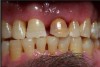

N.P.’s occlusal surfaces exhibited generalized extreme wear and/or erosion, and he complained of dentin hypersensitivity (Figure 2 and Figure 3). A caries risk assessment and diet recall was performed to assess the patient’s diet to determine its impact on the dentin hypersensitivity and caries risk. During the dietary assessment, N.P. reported severe GER problems limited his food selection.

Periodontal assessment revealed (Figure 4 through Figure 9):

• eneralized 4 to 6 mm probing depths on posterior teeth

• Furcation involvement, which included Grade I buccal of the maxillary left first and second molar and ML and Grade II buccal of the maxillary left third molar

• Tooth mobility – Class I maxillary left central incisor

• Bleeding Index: 39.8%

• Plaque Index: 100%

Figure 3  Mandibular Arch

Figure 3

Figure 4  Anterior View

Figure 4